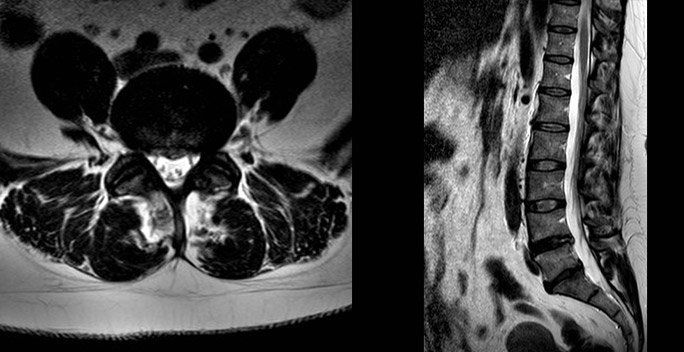

When do I need a re-scan?

The images below show a resolved disc prolapse. There is no longer black material in the spinal canal. Whether you need a new scan will depend on how you respond to treatment, clinical assessment and if it is felt you may benefit from an operation.

Can my disc prolapse heal itself?

Yes. The body has a remarkable capacity for repair. This prolapse resolved within 3 months. The body shrinks the disc by absorbing water, when this process is complete your pain will improve. The majority of discs will improve given long enough. My role is to guide you through the options, and step in if your life is on hold and waiting is unacceptable you may be a candidate for surgery on the lower back.